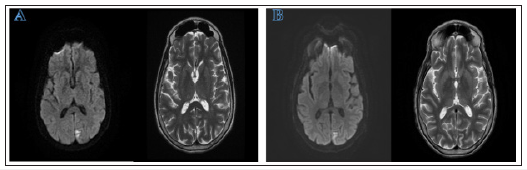

A 61-year-old right-handed female with a past medical history of localized amyloidosis, patent foramen ovale and genital HSV presented with complaints of new onset diminished and blurry vision bilaterally, image distortion, and difficulty focusing on objects. She denied eye pain, new headaches, and other neurological symptoms. Neurological exam was unremarkable, except visual field testing revealing homonymous right inferior quadrantic hemianopia and MRI showed left occipital diffusion restriction (Figure 1A). This led to an initial diagnosis of acute left posterior cerebral infarction. The patient returned 3 weeks later with complaints of worsened vision loss and increasing difficulty focusing on objects. She described her vision as being “weird” but could not offer more details. Repeat MRI was stable and repeat visual field testing showed worsening right lower quadrantanopia. The patient was started on valproate due to concern for focal seizure without impaired awareness. One week later, the patient returned with persistent decline in vision that was severely impacting her activities of daily living. She also reported that she was perceiving movement of objects that she knew were stationary and visual disturbances that she likened to those experienced when drinking too much alcohol. Around the same time, her family witnessed waxing and waning mental status accompanied by blank staring spells in the middle of conversations and a decline in short-term memory. Outpatient EEG showed brief slow and spike activity in the left occipital area accompanied by generalized slowing (Figure 2A).

Figure 1: MRI displaying small cortical diffusion restriction indicative of an acute to subacute infarction in the left occipital lobe. Side A displays the earliest MRI taken. Side B displays the latest MRI, performed five weeks after the first. No significant changes were noted on MRI in this timespan

In the next week, the patient showed worsening of her clinical focal seizure activity and was hospitalized. By this time, neurological exam showed partial central vision loss and right lower quadrantanopia. Repeat brain MRI showed stable left occipital signal on DWI without enhancement or worsening of cerebral edema (Figure 1B). Repeat EEG showed epileptiform discharge in the left occipital region and focal seizure activity. Over the following two days, the patient was noted to have continuous decline of consciousness progressing to an inability to follow commands. Repeat EEG at this time showed sustained rhythmic 2-3hz generalized spike-wave activity that was more organized in the left occipital region, raising concern for NCSE (Figure 2B).The patient was transferred to another facility and continued to be non-verbal, restless, and showing signs of altered consciousness. After arrival, exam showed intermittent jerking movement of all extremities lasting 3-5 seconds. cEEG showed NCSE with persistent focal epileptiform discharges in the posterior occipital regions. The patient was started on sedatives and five anticonvulsants, but complete cessation of clinical symptoms or recovery to normal mentality was never achieved.

This case also illustrates that various atypical neuro-imaging findings may present in patients with sCJD. DWI MRI is commonly performed to aid in diagnosis of sCJD. sCJD commonly presents as bilateral symmetric hyperintense cortical or sub-cortical areas, known as a “cortical ribbon” sign [9,10]. In HvCJD, a common radiological feature is a bilateral hyper-intense signal localized primarily to the occipital cortex seen on DWI MRI [10,11]. This is seen in many other cases involving a large area of the occipital cortex [2,11,12]. Additionally, some patients show an expanding area of hyper-intensity eventually infiltrating the parietal cortex [2]. In our case, the patient presents with a stable, localized hyperintense signal in the left occipital cortex. Interestingly, this area of hyper-intensity was not symmetrical and did not cross the midline. This small lesion led to the initial diagnosis of a left occipital ischemic stroke. It is important to note that this sCJD variant can present with atypical MRI findings including focal unilateral lesions. This finding shows how sCJD should be considered as a differential diagnosis even if the MRI findings are atypical.